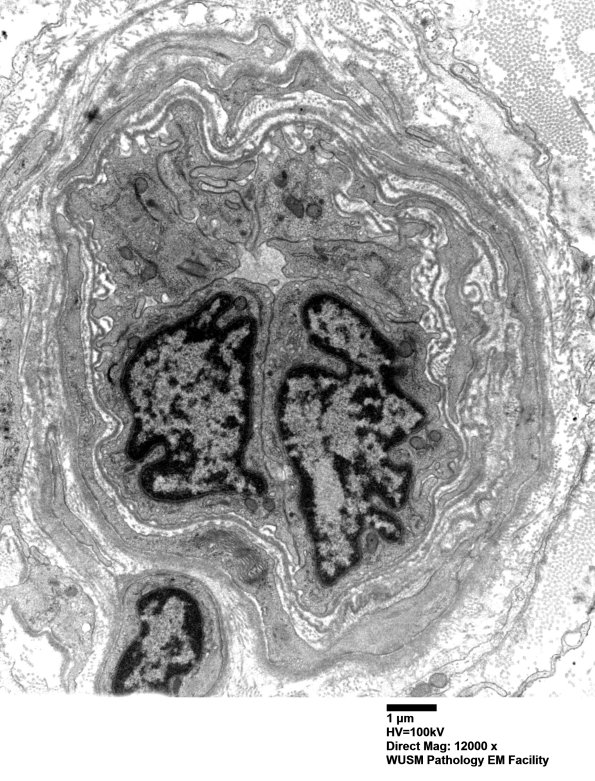

Washington University Experience | PERIPHERAL NEUROPATHY | 11 VASCULITIS - VASCULOPATHY | 2 Vasculopathy | 16B9 (Case 16) HIEM EM030 - Copy

16B9,10 There are numerous fragments of basal membranes within the abnormal vessel wall. (electron micrographs)